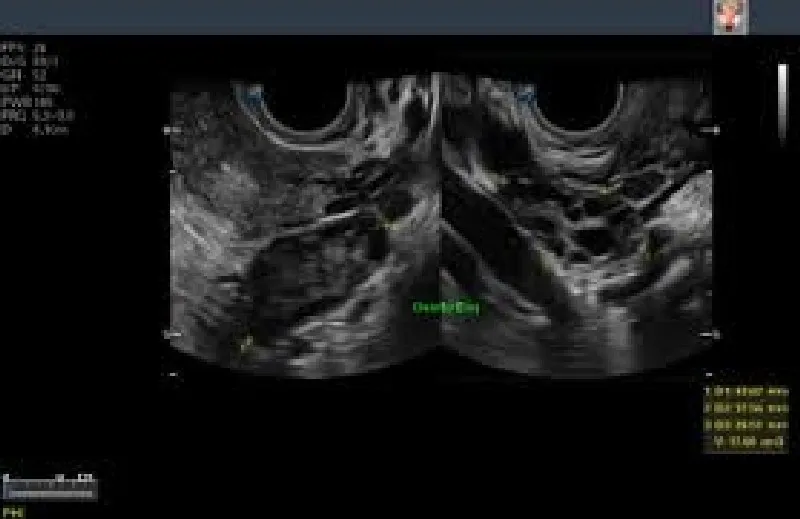

Com a possibilidade de ser alugada com uma empresa de outsourcing de impressão de alta confiabilidade, a impressora de ultrassom proporciona que as imagens deste exame, formadas por meio das ondas sonoras emitidas e captadas durante o processo, sejam impressas em alta qualidade no papel fotográfico, eliminando a necessidade de impressão em filme dry. O processo realizado com a impressora de ultrassom é veloz e permite que o profissional de medicina altere as imagens do exame antes da impressão, melhorando elementos como cor e contraste. Todos estes fatores contribuem para um diagnóstico mais rápido e preciso, o que beneficia o paciente e otimiza o tratamento.